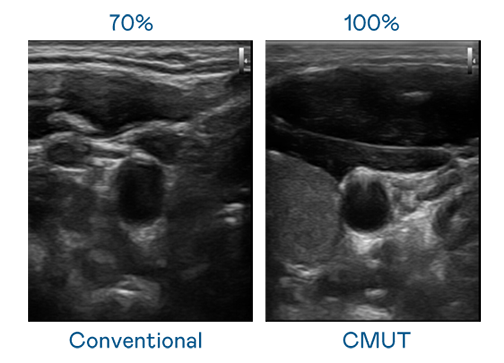

CMUT 技术是一种用电容式微机电元件来产生超音波讯号的技术。与传统 PZT 压电式技术相比,CMUT 频宽增加 30%,更宽频的超音波讯号让影像解析度大幅提升,是实现高影像品质医疗超音波扫描、促进精准医疗发展的关键技术。

大频宽带来超清晰影像

超音波影像的解析度高低,首先取决于探头能发出的讯号频宽。9001DCC金沙 CMUT 可提供高清晰的超音波讯号,提供高频宽、高灵敏度、影像纹理细节更高的超音波影像,协助医护人员缩短影像判读时间及利用精准的医疗影像进行诊断。